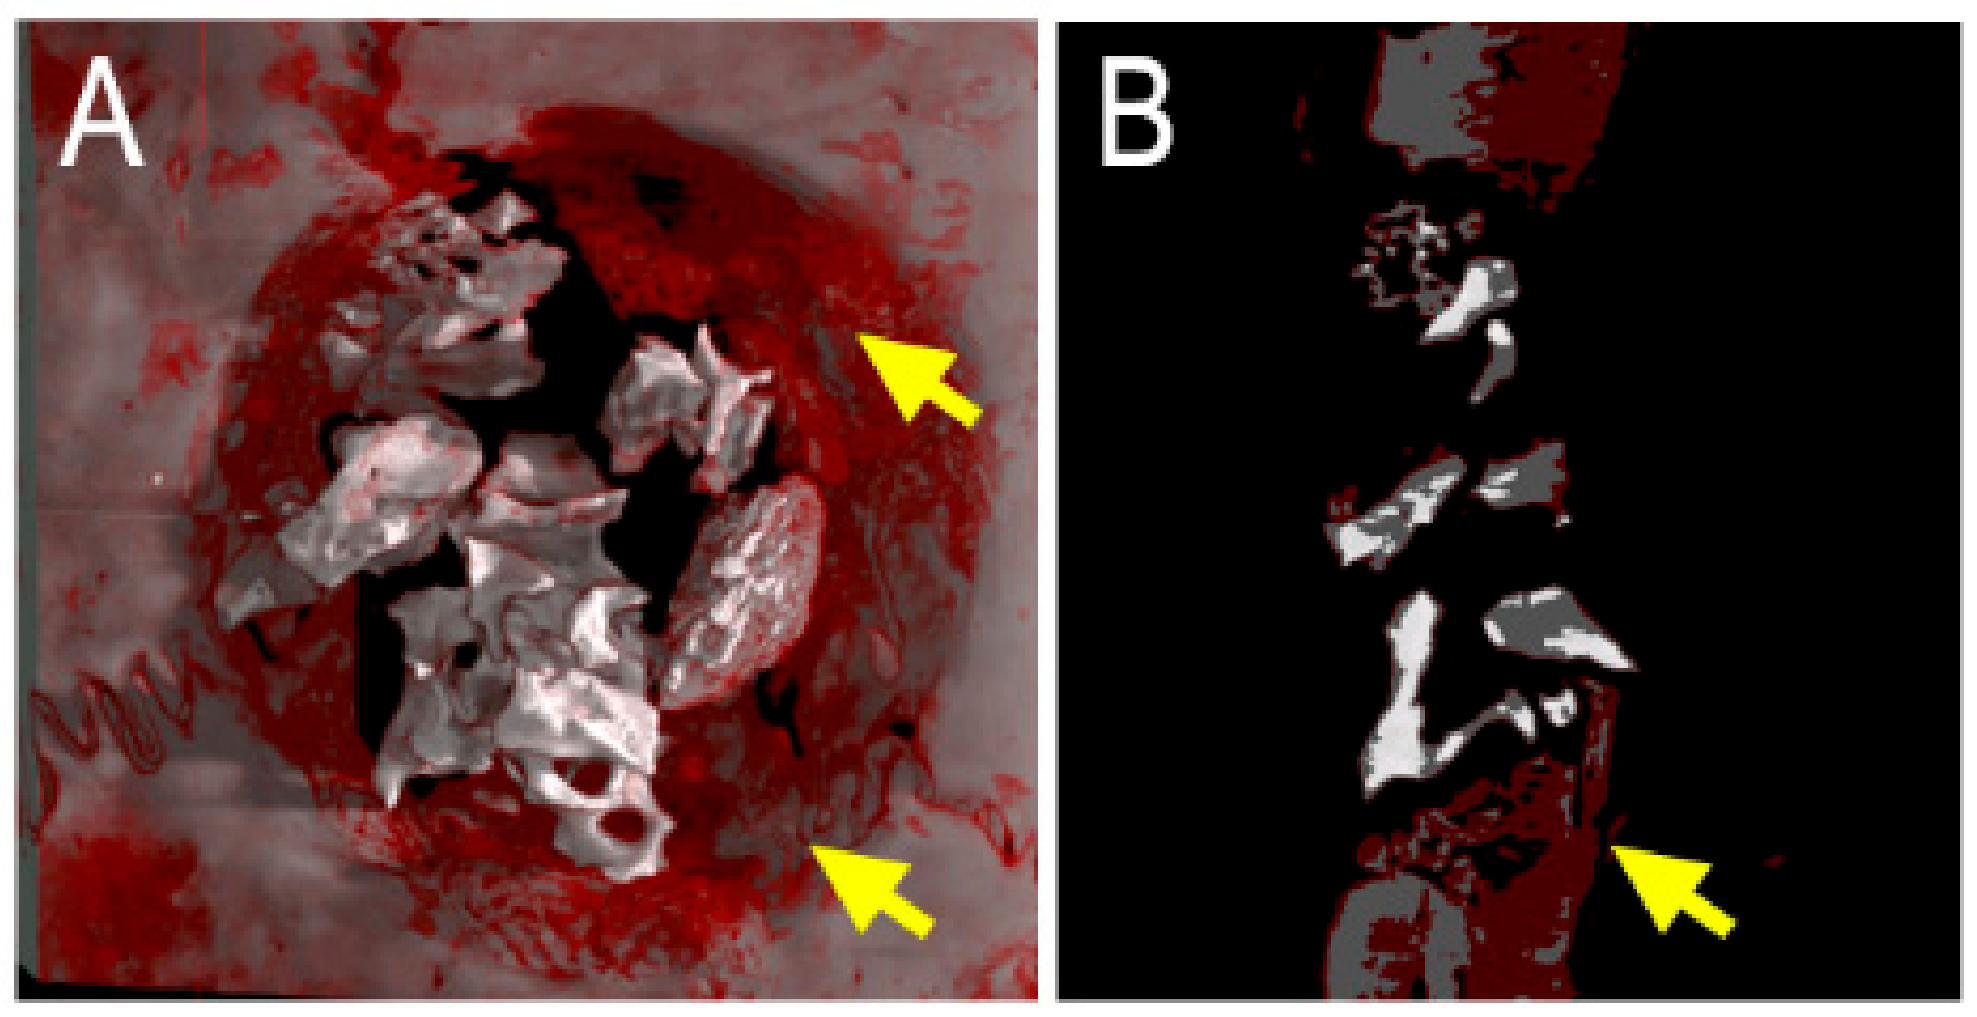

2.1. Synchrotron Radiation-Based Micro-Tomography